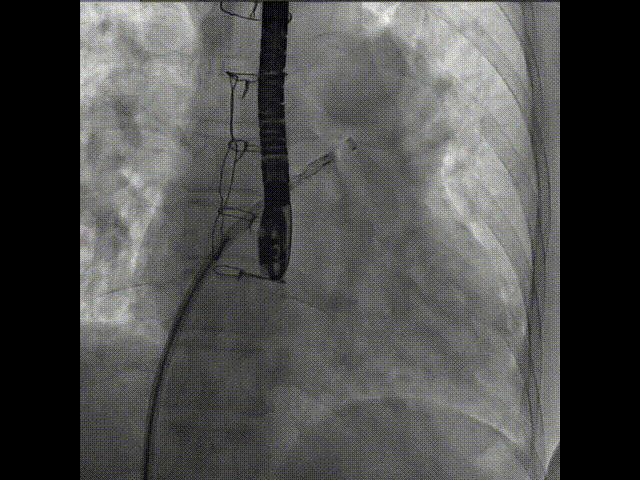

术中首先在局麻下穿刺股动脉、股静脉,完成心导管检查评估后转为全麻,在食道超声引导下穿刺房间隔,穿刺成功后将加硬导丝送入左上肺静脉建立轨道,根据患者病情行球囊预扩张后植入6mm孔径房间隔造孔支架,经透视及食道超声评估支架左右盘展开良好,夹持于房间隔两侧,固定稳定、位置良好,食道彩超显示房水平右向左为主分流,分流孔直径符合预期大小,心导管检查评估达到预期效果,释放造孔支架。术后12h患者下床活动,恢复顺利,拟于近日完善术后评估后出院。

图3.右盘在右房展开